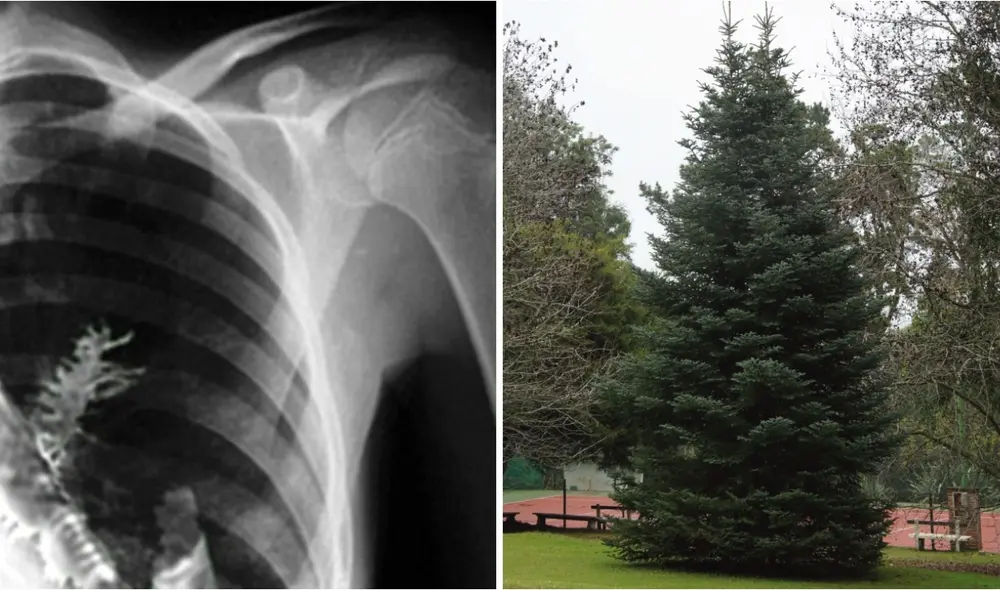

Historia. En 2009, Artyom Sidorkin (entonces 28 años) tosía sangre con frecuencia. Por sus fuertes dolencias en el pecho, decidió acudir al hospital de su Rusia natal. El primer examen que le hicieron fue una radiografía. Los médicos advirtieron un presunto bulto en el pulmón que, creyeron, parecía un tumor. El jefe del Centro de Oncología de Udmurtian, Vladimir Kamashev, tenía pocas dudas: se trataba de un cáncer.

Para confirmarlo, antes de operarlo, decidió aplicarle una biopsia. "No me lo podía creer... llamé a mi ayudante para que echara un vistazo", contó entonces Kamashev. En el tejido pulmonar vio unas cuantas agujas verdes clavadas.

Foto: KP.RU

Eran 5 centímetros de ramas de abeto, árbol de tronco alto y recto que puede elevarse hasta 60 metros. El oncólogo recordó haber parpadeado tres veces y pensar en un árbol de Navidad. Pronto planteó hipótesis.

Artyom no podía haberlo inhalado sin desgarrar algún músculo y provocar una hemorragia. Ni siquiera habría llegado al pulmón. La única opción fue que se tragó un minúsculo capullo de planta y que el fruto brotó en el órgano dañado.

"Me explicaron que estaba tosiendo sangre no por algún tipo de enfermedad, era solo que las agujas tocaban los capilares... Fue muy doloroso, pero, para ser honesto, ni siquiera sentí que hubiera algún tipo de cuerpo extraño en mí", declaró el paciente a la prensa rusa.